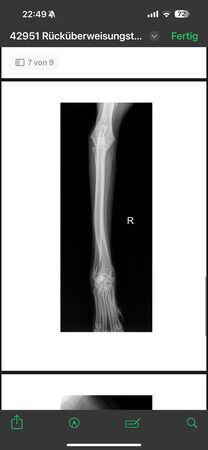

radiologisch kein Kniegelenkserguß oder Arthrose, nur Weichteilschwellung im Bereich distaler

Patellasehne, Elle proximal verdickt und Fehlstellung (alte, verheilte Fraktur?), keine deutlich

Ellbogenarthrose, leichtgradige Fehlstellung Unterarm li., auch leichtgradige Fehlstellung Radius re.

Alle Gelenke sonst ohne deutliche Arthrosezeichen.